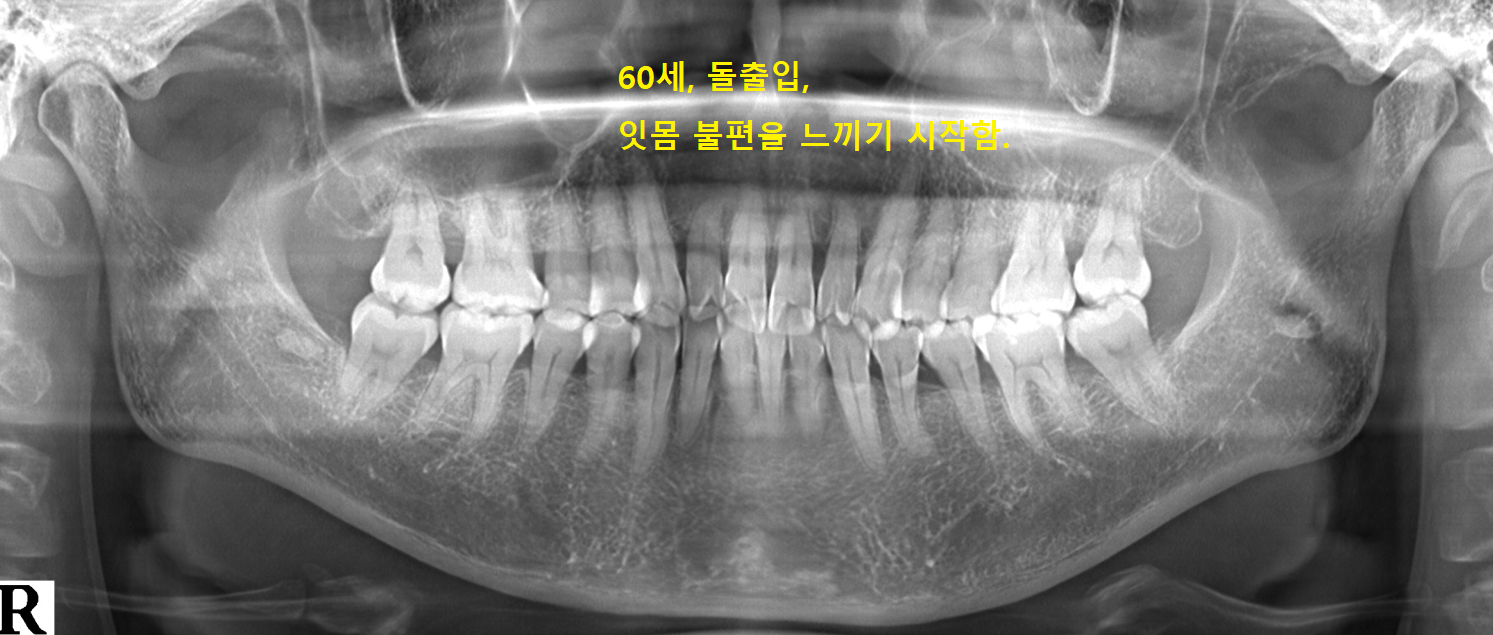

전형적인 돌출입 얼굴,

태어난 대로 살아옴.

치과를 거의 안 다님.

60세가 되어 잇몸이 안 좋아지는 것을 느낌.

천천히 잇몸이 나빠질 것으로 보임.